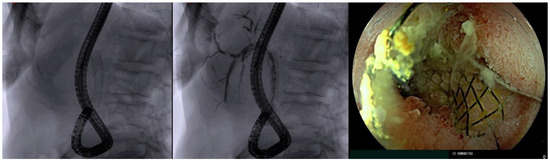

6. EDGE (EUS-Directed Transgastric ERCP) Procedure

- Anderloni, A.; Fugazza, A.; Spadaccini, M.; Colombo, M.; Capogreco, A.; Carrara, S.; Maselli, R.; Ferrara, E.C.; Galtieri, P.A.; Pellegatta, G.; et al. Feasibility and safety of a new dedicated biliary stent for EUS-guided hepaticogastrostomy: The FIT study (with video). Endosc. Ultrasound 2023, 12, 59–63. [Google Scholar] [CrossRef] [PubMed]